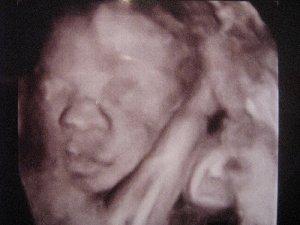

Es ist alles gut. Keine Wehen oder dergleichen!! Mir gehts auch mittlerweile besser, Blut wurde abgenommen. Mal schauen, wie die Eisenwerte diesmal waren. Habe auch wieder ein 3D Bild bekommen. Er sieht immer mehr aus, wie sein großer Bruder, nur dass er vollere Lippen hat. In 4 Wochen ist wieder großer US angesagt, mit ausmessen. Da bin ich echt mal gespannt. Hoffe so sehr, dass er nicht so schwer und groß wird, wie sein großer Bruder, denn sonst kann ich mich wahrscheinlich wieder auf einen Kaiserschnitt einstellen und das WILL ich nicht!!! LG Peach

oh ist der süß .. der hat ja wirklich nen schmollmund ;D wie süüüß :D und hast dus schön wegen den fotos hab seit der 11 ssw kein foto mehr bekommen da sich der zwerg imme rnur versteckt hat ;( weiß nedmal wie das gesicht aussieht ... menomensch